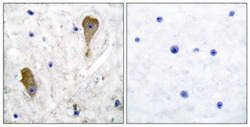

Supportive validation

- Submitted by

- Aviva Systems Biology (provider)

- Main image

- Experimental details

- Immunohistochemical analysis of paraffin-embedded human brain tissue using GAD67 antibody. The picture on the right is treated with the synthesized peptide.